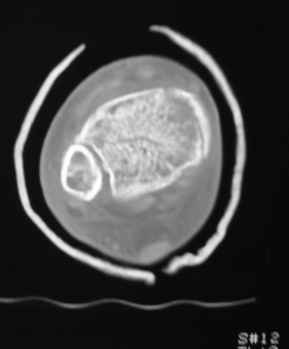

Остеопороз (продолжение 3) - данные КТ

Продолжая тему представляю данные КТ нашей пациентки.